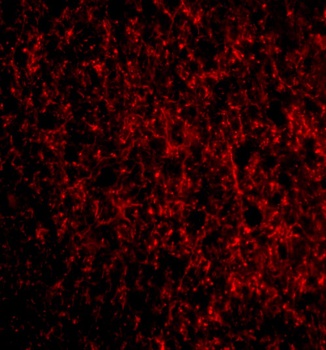

Immunohistochemical staining of human testis tissue using TMED10 antibody